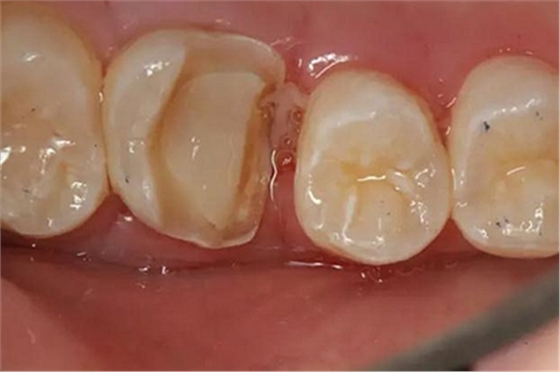

病例一 女性,20歲,大學(xué)生,要求補牙,檢查口內(nèi)可見A6大面積缺損,近中牙齦息肉,拍X片,根管充填物略差,但根周未見明顯陰影,口內(nèi)檢查無叩痛。建議患者冠延長手術(shù)+高嵌體修復(fù)。

患牙遠(yuǎn)中邊緣嵴完整,強度沒有降低,故擬保留遠(yuǎn)中邊緣嵴,高嵌體修復(fù)。首先去除腐質(zhì)及原墊底材料,流體樹脂+3M Z350XT樹脂墊底。局麻下行冠延長手術(shù)。在此需要提及個人的一個觀點。冠延長手術(shù)原則上要求3-6個月以上才能永久修復(fù)。但是個人喜歡后牙肩臺建立在齦上,所以修復(fù)后的修復(fù)體邊緣位于牙齦上方1mm,對牙周的愈合影響較小(如果為齦下邊緣則要慎重),故該患者術(shù)中按照齦上邊緣的設(shè)計進行冠延長手術(shù)。以下為術(shù)中: